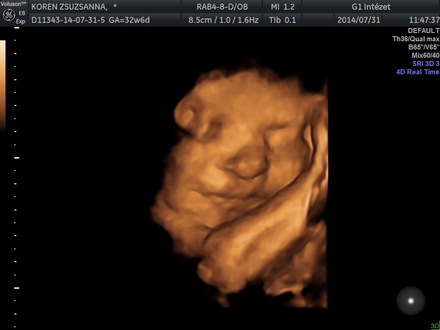

Született: 2014. 9. 17., Kistarcsa,

Meghalt: 2014. 9. 17., Kistarcsa

Mindig a szívünkben maradsz! Nagyon Szeretünk! Apukád és Anyukád

Krisztián